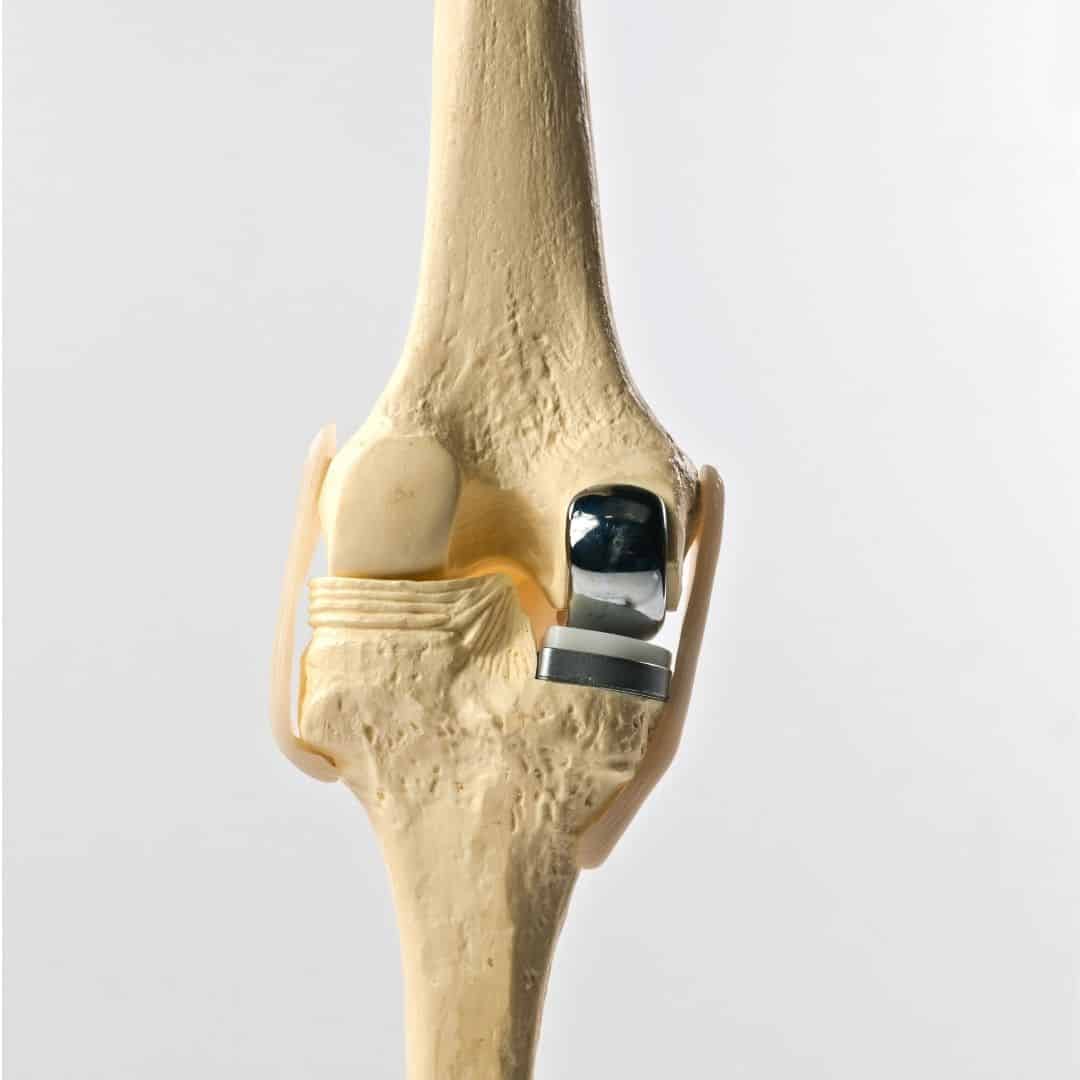

Partial knee replacement, also known as unicompartmental knee arthroplasty, is a surgical procedure aimed at treating arthritis confined to a single compartment of the knee. Unlike total knee replacement, which involves replacing the entire knee joint, partial knee replacement targets only the damaged area, preserving the healthy parts of the knee. This procedure is typically recommended for patients with osteoarthritis that affects only one side of the knee, either the medial (inner) or lateral (outer) compartment, while the rest of the knee remains relatively healthy.

During the surgery, the orthopedic surgeon makes a small incision over the knee and removes the damaged bone and cartilage from the affected compartment. These are then replaced with metal and plastic components designed to mimic the natural movement of the knee. The goal is to relieve pain and improve function while maintaining as much of the natural knee structure as possible. One of the significant advantages of partial knee replacement is that it is less invasive than total knee replacement, resulting in a shorter hospital stay, faster recovery, and less postoperative pain.

Partial and total knee replacements are surgical procedures designed to alleviate pain and restore function in patients with severe knee arthritis, but they differ significantly in their approach and scope. This procedure is less invasive, preserving more of the patient's natural knee structures, including the ligaments. In contrast, total knee replacement involves replacing all three compartments of the knee: the medial, lateral, and patellofemoral (front) compartments. This procedure is recommended for patients with widespread arthritis affecting the entire knee joint. During the surgery, the damaged bone and cartilage are removed and replaced with metal and plastic components designed to mimic the natural movement of the knee.